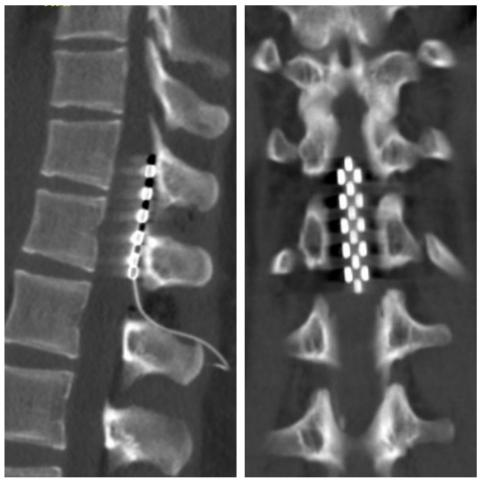

经过全面细致的评估,团队判断该患者仍具备较好的神经功能恢复潜力,遂为其制定了“脊髓电刺激(SCS)植入术”治疗方案。手术于胸11-腰1节段成功植入片状电极,术中电生理监测反应良好,术后患者恢复顺利。令人欣慰的是,在首次启动刺激后,患者立即感受到微电流传向下肢,提示神经调控已初步起效。

5-6-5片状电极位置